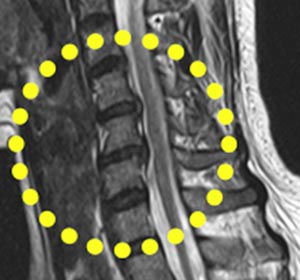

목디스크 치료 방법: 목디스크 초기증상 치료는 대개 약물 치료와 물리 치료를 아울러하면서 증상의 완화를 관찰하고요. 목디스크 환자의 90% 정도는 약물 치료와 물리 치료로 6개월 내 호전되기도 합니다 초기에 효과가 없는 경향에는 수술적 치료를 시행하는데요. 신경 차단술, 인공 디스크 삽입, 내시경 수술 방법 등이 있습니다.

목디스크 운동요법: 목디스크에 좋은 운동은 어떠한 것들이 있을까요? 평소에 목과 어깨를 수시로 해결해주는 운동을 하고 근로할 때 자세를 자주 바꿔주는 것이 바람직해요. 걷기 운동도 도움이 가득히 됩니다. 그리고 목디스크 스트레칭으로는 갸우뚱 체조, 목베개 체조, 꽈배기 체조 등을 쉽게 찾아 볼 수 있습니다. 또한 보존적 요법으로 목디스크 베개를 사용하는 것도 도움을 준다고하였습니다.